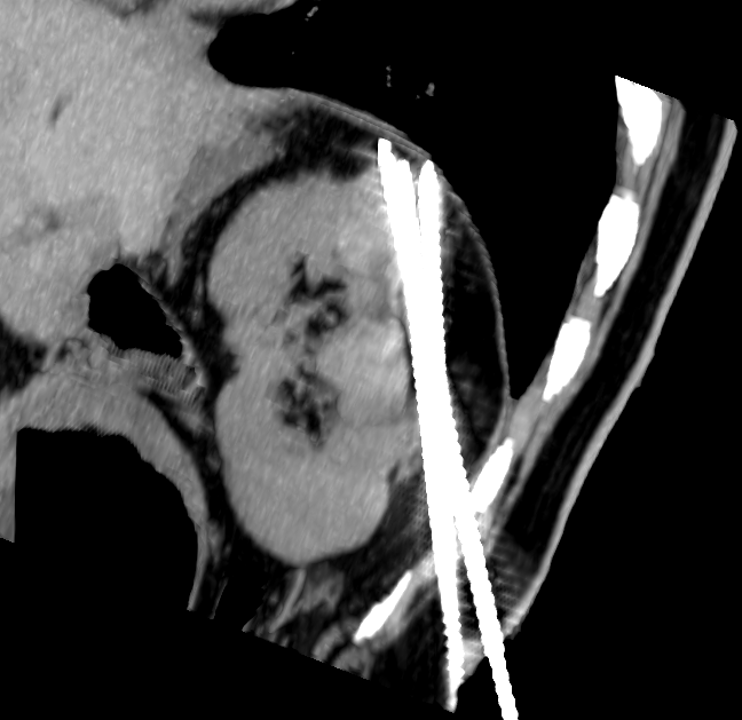

Renal upper pole lesion ablations

Renal upper pole lesions are theorized to be more difficult to ablate and potentially with lower rates of disease control and higher risks of complications. We are doing a retrospective chart review project to demonstrate that ablations of renal upper pole lesions are just as safe and effective.